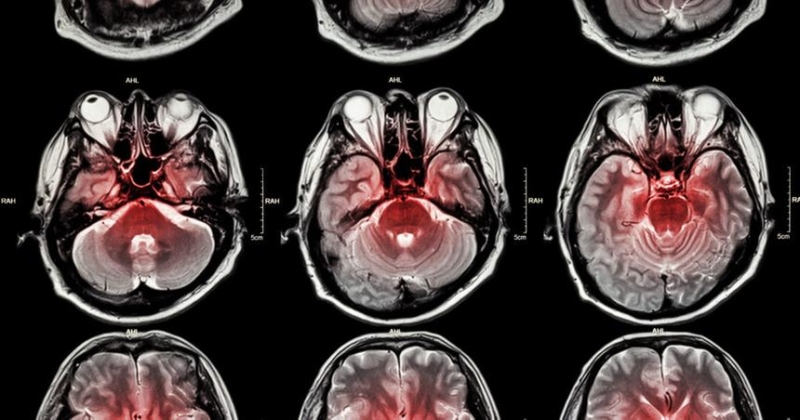

Инсульт — основная причина смерти во всём мире, а в последние годы это состояние стало встречаться чаще. В рамках новой научной работы исследователи выяснили, связан ли индекс здоровья TyG-WWI с риском возникновения инсульта среди населения в целом.